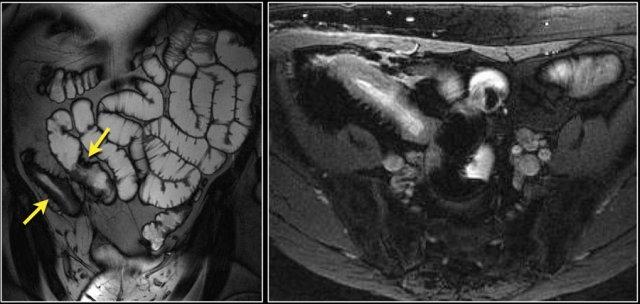

Các hình ảnh cho thấy một khối phát triển theo chu vi với bờ dạng vai.

Ung thư biểu mô tuyến kích thước lớn có thể bắt chước hình ảnh u lympho như trong trường hợp này.

Các hình ảnh cho thấy một khối không đều ở đoạn gần hỗng tràng.

Mặc dù là khối phát triển theo chu vi với kích thước lớn, lòng ruột không bị tắc nghẽn.

Có một khối hạch bạch huyết tập hợp lớn giảm tỷ trọng ở mạc treo lân cận, phù hợp với di căn hạch bạch huyết hoại tử (hình dưới).

Kết quả giải phẫu bệnh xác nhận là ung thư biểu mô tuyến, nhưng các dấu hiệu này cũng có thể rất phù hợp với u lympho.

Đây là hình ảnh nội soi của khối u.

Đây là bệnh nhân có dày thành lan rộng ở đoạn gần hỗng tràng kèm giãn phình dạng túi phình.

Chẩn đoán hàng đầu trong danh sách chẩn đoán phân biệt của chúng tôi là u lympho, nhưng kết quả giải phẫu bệnh xác nhận là ung thư biểu mô tuyến.

Các đặc điểm gợi ý ung thư biểu mô tuyến là thâm nhiễm mỡ mạc treo (fat stranding) và di căn hạch bạch huyết.

Trong u lympho, thâm nhiễm mỡ ít gặp, nhưng di căn hạch bạch huyết vẫn xảy ra và thường có kích thước lớn hơn.